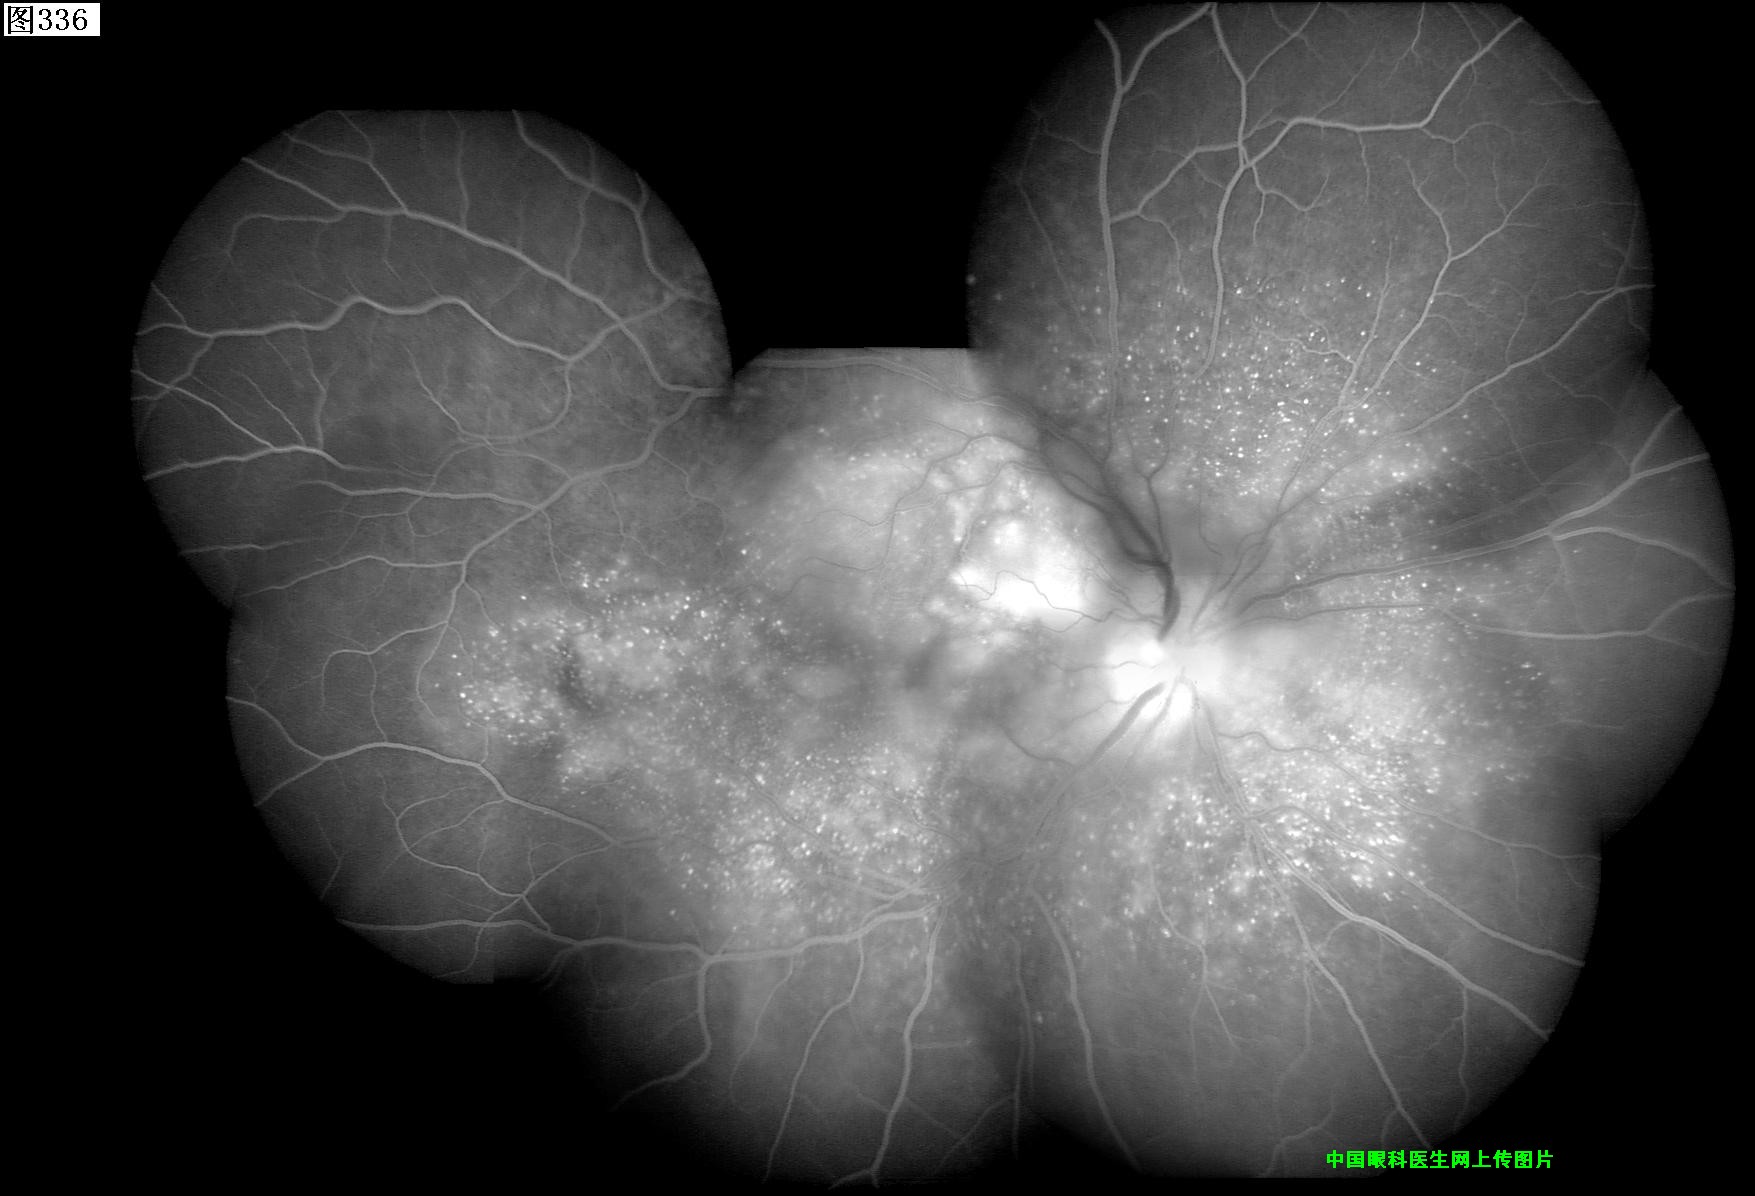

333 334 335 336